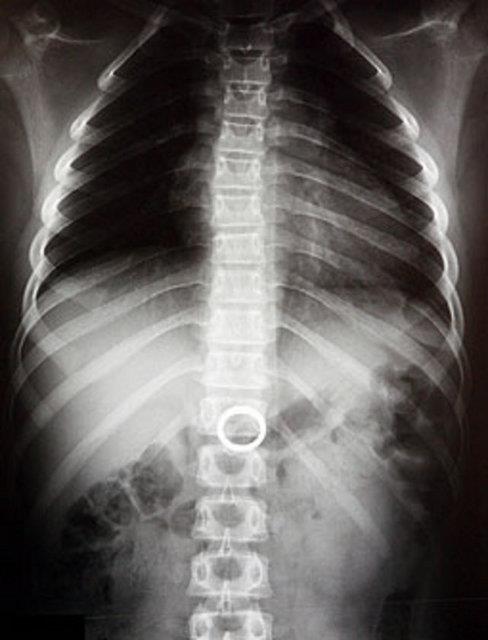

11. Yemek borusuna metal para sıkışmış bir çocuğun röntgeni...

Yemek borusuna metal para sıkışmış bir çocuğun röntgeni...